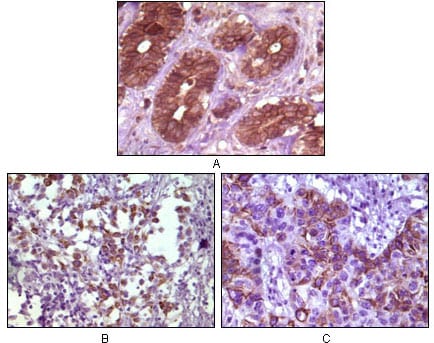

分类: 科研抗体货号: 20104别名: BP-1; 4EBP1; 4E-BP1; PHAS-I; MGC4316; EIF4EBP1应用: IHC反应种属: Human